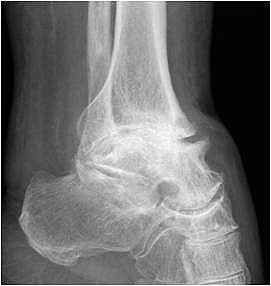

• Primäre oder posttraumatische Arthrose des OSG und USG (Abbildung 1, Abbildung 2).

• Revision einer gescheiterten Fusion des OSG/ USG (Abbildung 3, Abbildung 4).

• Standard-Röntgendiagnostik des oberen und unteren Sprunggelenkes: anterior-posteriorer und seitlicher Strahlengang.